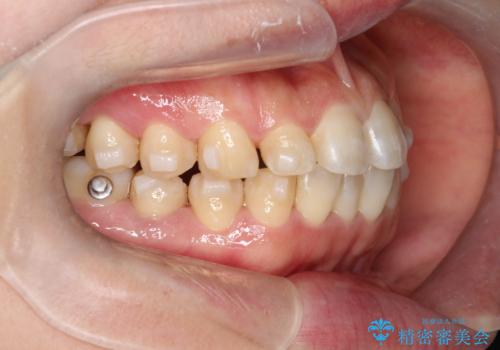

【インビザライン】前歯のすきまを閉じたい

- 前歯の隙間を主訴に来院されました。

インビザライン にて治療を行い、歯並びを改善することができました。